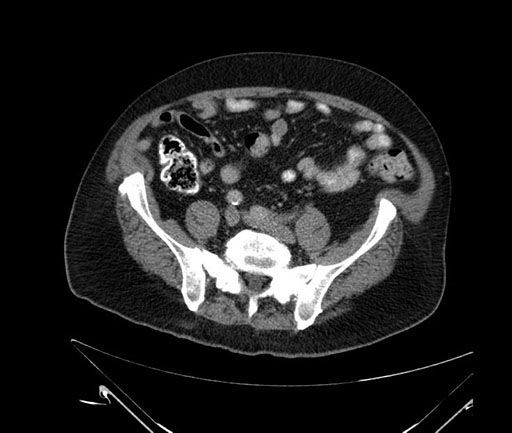

Whipple (pancreaticoduodenectomy) [case 7]

Axial - 3 months prior

Imaging analysis

Based on your CT findings, which issue(s) would give reason for "planned slowing down moment(s)" in this case?

Considering a standard Whipple procedure, what step(s) of the operation would you do differently in this case?